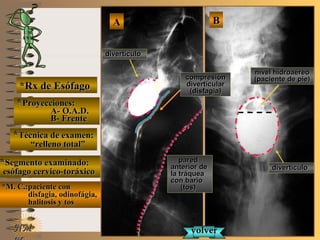

*Rx de Esófago*Rx de Esófago

**Proyecciones:Proyecciones:

**Técnica de examen:Técnica de examen:

**Segmento examinado:Segmento examinado:

*M. C.:paciente con*M. C.:paciente con

disfagia, odinofágia,disfagia, odinofágia,

halitosis y toshalitosis y tos

BBAA

O.A.D.O.A.D.

FrenteFrente

““relleno total”relleno total”

esófago cervico-toráxicoesófago cervico-toráxico

A-A-El examen es normal o patológico?El examen es normal o patológico?

Examen patológico de esófago toráxico superiorExamen patológico de esófago toráxico superior

con técnica de relleno total en proyecciones:con técnica de relleno total en proyecciones:

A- O.A.D. y B- frenteA- O.A.D. y B- frente

B-B-La patología es congénita o adquirida?La patología es congénita o adquirida?

Patología adquiridaPatología adquirida

C-C-Dicha patología es orgánica, funcional o mixta?Dicha patología es orgánica, funcional o mixta?

**OpciónOpción

D-D-La misma es neoplásica o no neoplásica?La misma es neoplásica o no neoplásica?

Patología adquirida orgánica no neoplásicaPatología adquirida orgánica no neoplásica

E-E-Puede describir la o las imágenes patológicas?Puede describir la o las imágenes patológicas?

Se identifica unaSe identifica una imagen de adición o deprimidaimagen de adición o deprimida

UNTUNT (ver(ver TerminologíaTerminología UNTUNT )) divertículo de Zen-divertículo de Zen-

ker en esófago cervical, sobre el borde posterior,ker en esófago cervical, sobre el borde posterior,

y se distingue también “pintado” con bario a lay se distingue también “pintado” con bario a la

pared anterior de la tráqueapared anterior de la tráquea

A- O.A.D.A- O.A.D.

B- FrenteB- Frente

divertículodivertículo

volvervolver

paredpared

anterior deanterior de

la tráqueala tráquea

con bariocon bario

(tos)(tos)

nivel hidroaéreonivel hidroaéreo

(paciente de pie)(paciente de pie)compresióncompresión

divertículardivertícular

(disfagia)(disfagia)